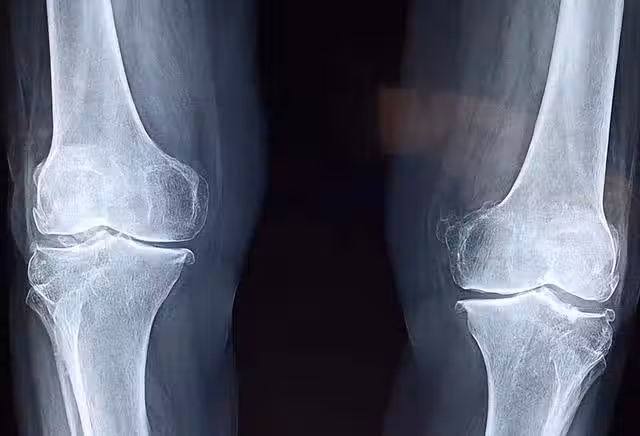

存在這4種情況的人,可能會讓補的鈣片白白浪費

一看產品的含鈣量

在選擇鈣片時不能只是看說明書上的劑量,而應當了解其含有鈣元素的量。一般而言,鈣製劑標註鈣含量有兩種方式:一種是含鈣化合物的量,另一種是含有鈣元素的量。

後者才是真正攝入的鈣量。